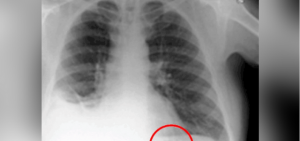

Esta mancha en la radiografía anunciaba un aparente tumor en el pulmón, pero tras analizarla la noticia se transformó y se volvió un tanto aliviador para todos.

Después de examinar al paciente lo que encontraron en su pulmón fue algo sorprendente pues era un juguete “Playmobil” lo que formaba esta mancha.

El paciente tragó una pieza cuando tenía 7 años, lo que sorprendió a todos los doctores pues haber vivido con esto durante 40 años fue grave, sin haber tenido síntomas de algo, tos constante o alguna molestia en la parte del pulmón.